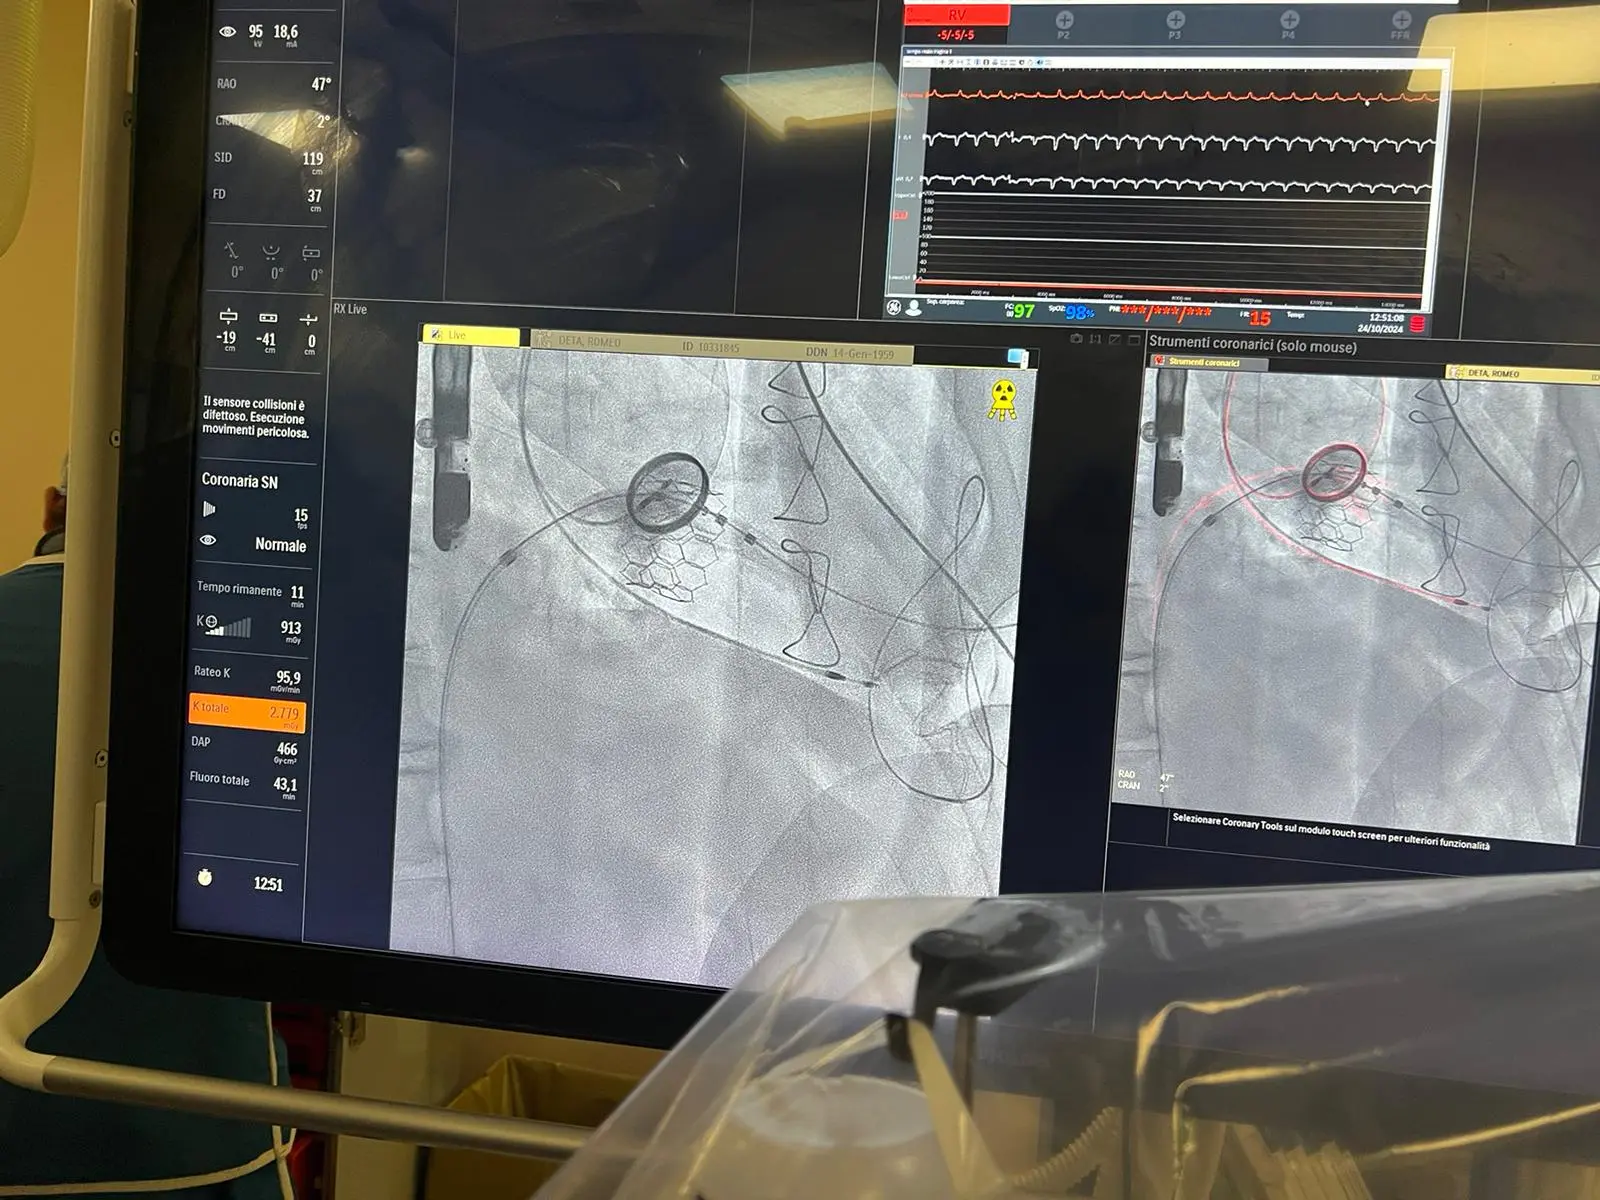

“La procedura standard di sostituzione della valvola mitralica può essere percutanea con accesso trans-femorale, ovvero attraverso la vena femorale, o trans-apicale, ovvero con un’incisione del torace di 4-5 centimetri, praticata a livello dello spazio intercostale – spiega il prof. Giuseppe Nasso -. Nel caso specifico della paziente entrambi gli approcci se utilizzati in maniera isolata avrebbero comportato un elevato rischio di complicanze: la via trans-apicale da sola, infatti, risultava troppo invasiva (per il diametro ampio della nuova protesi) mentre l’approccio trans-femorale troppo poco stabile, con il rischio che la valvola biologica aprendosi si disallineasse all’interno del ventricolo. Abbiamo quindi studiato una procedura percutanea con ultra mini-toracotomia (un taglio estremamente ridotto sul torace) per raggiungere l’apice del ventricolo sinistro in cui è stata introdotta una guida molto sottile. Successivamente, è stata fatta passare una seconda guida dalla vena femorale che è stata poi unita alla prima attraverso un “cappio” creando così una vera e propria “teleferica” con partenza dalla vena femorale e uscita dall’apice del ventricolo sinistro. Su tale teleferica la valvola biologica “balloon expandable” ha potuto viaggiare, entrando dalla vena femorale sino a raggiungere l’anello mitralico, su cui è stata posizionata ripristinandone il corretto funzionamento”.

MyVal è una valvola cardiaca transcatetere di nuova generazione espandibile tramite palloncino, che grazie alle dimensioni ridotte delle cannule, alla maggiore precisione dell’impianto e alla sua maneggevolezza consente una migliore manovrabilità attraverso arterie di calibro ridotto e un dispiegamento preciso. Queste caratteristiche, combinate con una strategia chirurgica mai impiegata prima in Italia, hanno consentito di poter intervenire sulla paziente efficacemente e in sicurezza.